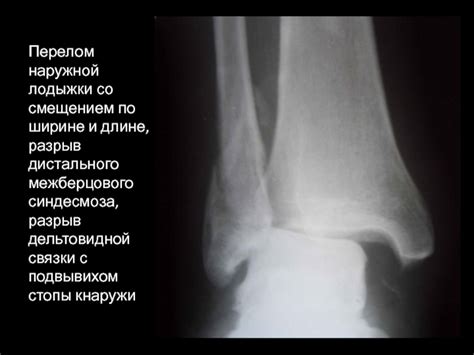

Перелом лодыжки описание рентгена

Перелом лодыжки со смещением

Перелом лодыжки со смещением: разновидности, ре...